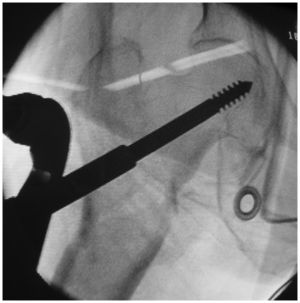

Surgical techniqueAfter basic fracture reduction, the PCCP was inserted with a 2-cm skin incision. After adjusting the plate position, the first neck screw was inserted into the appropriate position in the femoral neck, with the entrance point avoiding the fracture line (to avoid splitting and re-displacement in the proximal fracture when drilling) (Figures1) and 2). Then, three shaft screws were fixed through the second incision. Finally, the second neck screw was placed in the same way as the first screw. The wound was irrigated and closed without the use of a suction drain.

Intraoperative photograph of one patient. The PCCP was inserted in a submuscular manner and temporarily fixed with a butterfly pin and percutaneous bone hook to the femur via the proximal and distal incisions, respectively. The main sleeve was brought through one of the oblique holes in the proximal plate.